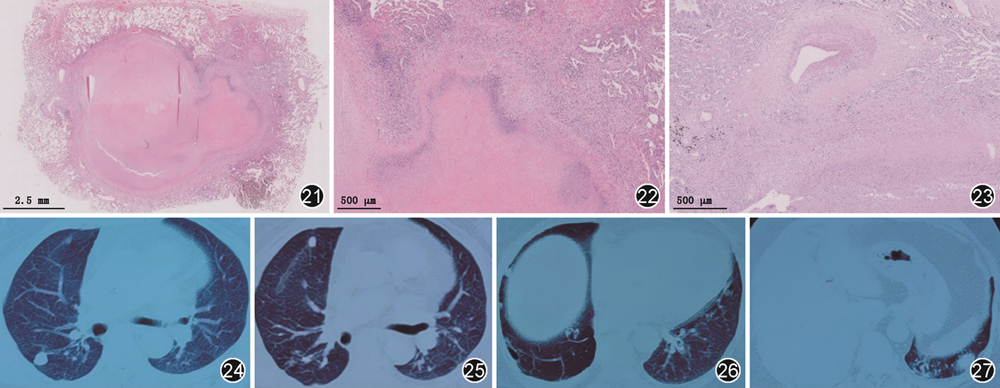

为进一步明确诊断,将北京胸科医院右肺下叶切除术后病理送至北京协和医院病理科会诊(图21, 22, 23)。

冯瑞娥(北京协和医院病理科):该病例镜下可见肺组织内大片退变坏死,坏死形状不规则、层状分布,中心嗜酸性、周边嗜碱性,坏死周边见上皮样细胞及多核巨细胞围绕,部分区域内见中性粒细胞核碎,病变周围见血管壁炎症细胞浸润,血管壁增厚,部分管腔闭塞,符合肺类风湿结节。特殊染色(PAS、抗酸、六胺银染色)均阴性。

很多肺部疾病可表现为肉芽肿病变,其病理诊断需要结合病变的分布,肉芽肿形态及伴随病变。组织病理学方面需鉴别以下疾病:(1)感染性肉芽肿性肺疾病,如结核分枝杆菌感染可见干酪样坏死,周围伴有上皮样组织细胞、朗格汉斯巨细胞、淋巴细胞等的浸润,抗酸染色可查找抗酸杆菌。如真菌感染,病理可见真菌菌丝和孢子,PAS、六胺银染色可呈阳性。(2)非感染性肉芽肿性肺疾病,以过敏性肺炎和结节病最为常见。过敏性肺炎多表现为以细支气管为中心的富细胞性间质性肺炎、非坏死性松散的肉芽肿结节以及小灶状肺泡腔内机化[7]。结节病的病理特征以非坏死性肉芽肿为其特点,为局灶性、慢性炎症反应,病变多沿淋巴管分布,肉芽肿结节排列紧密,其周边伴有显著纤维组织增生及玻璃样变。结节病可观察到中心区域纤维素样坏死,但大量坏死往往提示坏死性结节病样肉芽肿病或其他疾病[8]。坏死性结节病样肉芽肿病典型病理表现为单个的非干酪样肉芽肿性炎及由其聚集而成的病灶取代肺实质,形成灶性的肺实质坏死和以血管壁和肺实质为主的肉芽肿性血管炎[9]。对于既往支气管镜及CT引导下肺穿刺活检病理结果未能明确诊断的原因考虑为穿刺活检组织块过小所致。